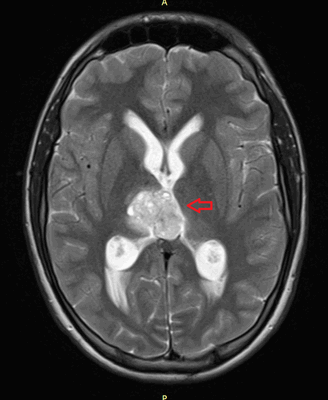

Головной мозг

Герминогенные новообразования в данной области - это примерно 2-4% от всех внутричерепных (интракраниальных). Патология в 75% случаев диагностируется у мальчиков, за исключением турецкого седла, где новообразования в основном локализуются у девочек.

Герминомы формируют инфильтрирующие опухоли больших размеров, часто являющиеся источниками субарахноидальных (между мягкой и паутинной оболочками мозга) и вентрикулярных (желудочковых) метастаз.

Рисунок 7. - Герминома головного мозга.

Рисунок 9. - метастаз в головной мозг при герминогенной опухоли.

Лечение

Герминогенные опухоли центральной нервной системы (головного мозга) имеют следующие клинические проявления: головная боль, расстройство движений глазных яблок, тошнота, рвота и развитие судорог.

Также выполняют МРТ головного мозга, чтобы выявить наличие метастазов в нем.

![Метастаз в головной мозг при герминогенных опухолях (МРТ головного мозга)]()

Метастаз в головной мозг при герминогенных опухолях (МРТ головного мозга)